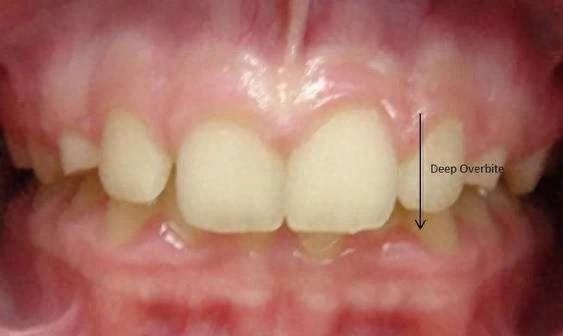

深覆合是一种上下颌牙弓,或上下颌骨垂直向发育异常所导致的错颌畸形。也就是在我们咬牙时,下牙被上牙全部盖住,或只露出很少一部分,就可以判断为深覆合。

娱乐圈中刘亦菲就是一个典型的例子,不笑的时候美的脱俗,一旦笑起来上牙几乎完全盖住下牙,并暴露过多的牙龈,这就是深覆合典型的例子。